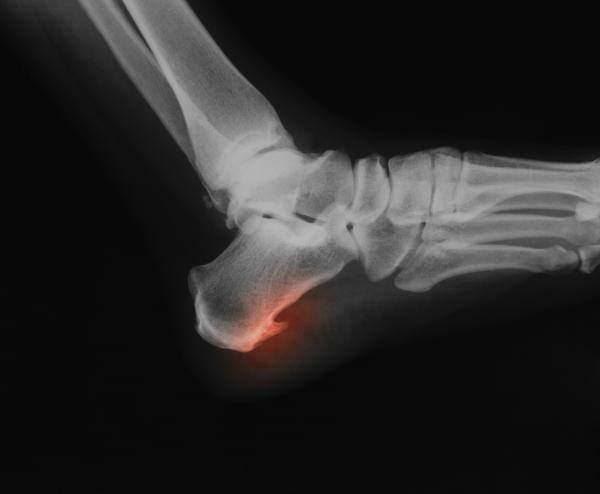

Es un crecimiento del hueso del talón en forma triangular o de lanza.

Si presentas estos síntomas visita a tu médico. El diagnóstico se realiza mediante la visualización del espolón en una radiografía.